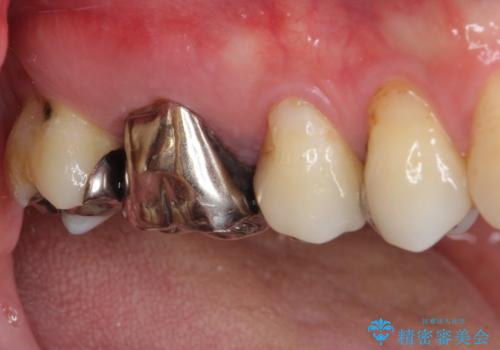

- 上の奥歯に咬んだときの痛みを感じて来院された患者様です。

まずは根管治療を行い、その後フルジルコニアクラウンにて補綴することとしました。